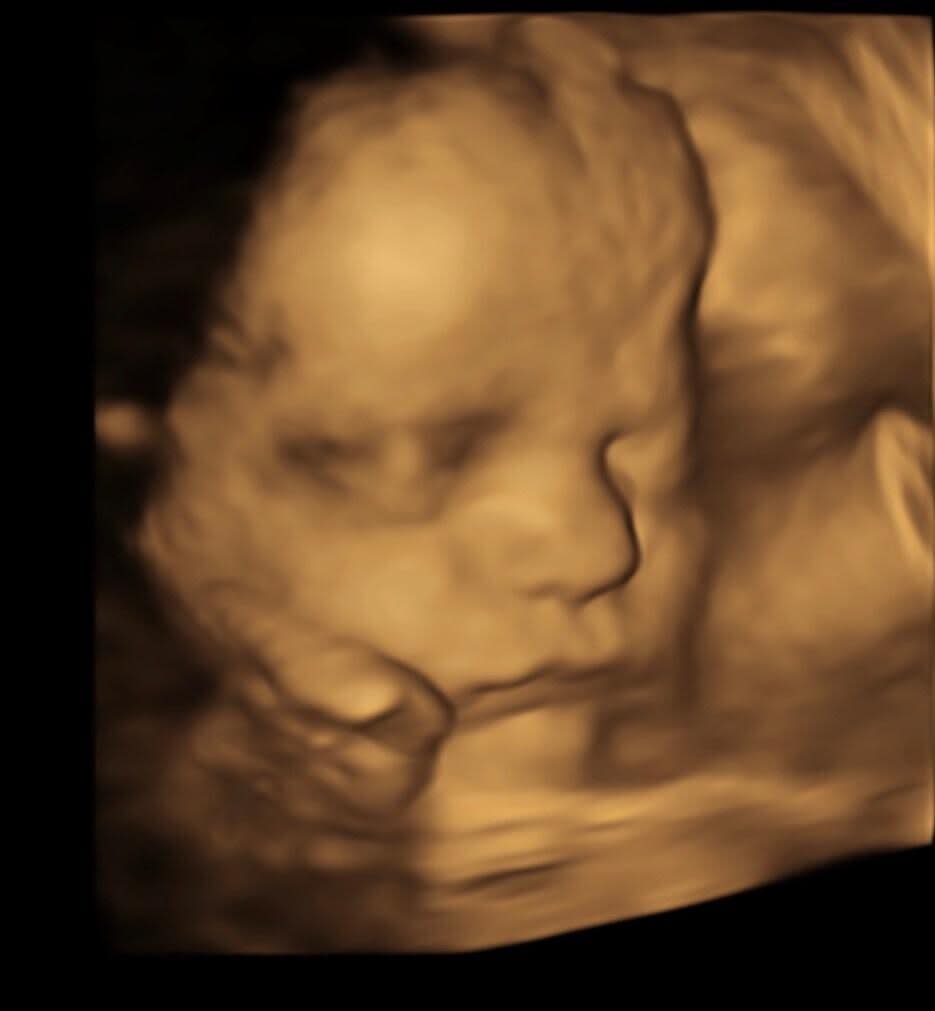

8K Enhanced Images

Grimsby Numi Scan are proud to use 8K technology combined with advanced AI techniques to digitally enhance your ultrasound images. This optional extra enhances 4D images to truly reflect your babies features and create a life like image for parents to be.

This service is carried out after your 4D ultrasound and is not new ultrasound technology but a way of upgrading and enhancing your 4D images. The turn around time is just 24 hours so we won't keep you waiting too long!

This service will work best on 26 weeks gestation and onwards.